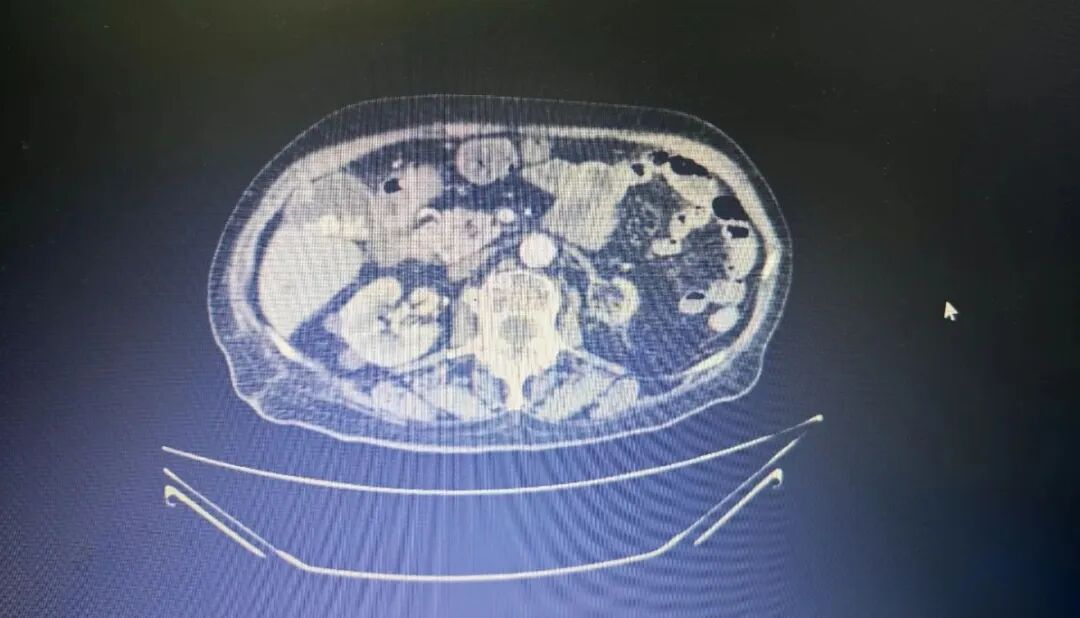

CT下病灶

患者91岁高龄,基础疾病较多,术前临床诊断达20多个,包括结肠恶性肿瘤、不完全性肠梗阻、贫血、高血压、冠状动脉硬化、肺气肿、肾功能不全、痛风、肺炎等多种疾病交织,病情复杂。

尤其是结肠癌合并脓肿及不完全性梗阻,胆囊结石伴胆囊炎,随时可能引发感染加重、穿孔、脓毒症等危象;而患者同时存在的动脉硬化、髂动脉血栓,更如同“定时炸弹”,术中术后随时可能因血栓性疾病导致危及生命;加上肾功能不全、痛风等,使得麻醉和手术风险增加。